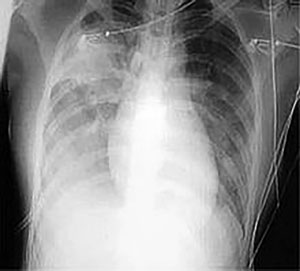

X-quang một bệnh nhân SARS

Hội chứng hô hấp cấp tính nặng (SARS), là bệnh đường hô hấp gây viêm phổi không điển hình ở những người bị nhiễm. Viêm phổi không điển hình gây sưng và suy yếu phế nang, làm giảm cung cấp máu tại chỗ cũng như ức chế vận chuyển oxy.